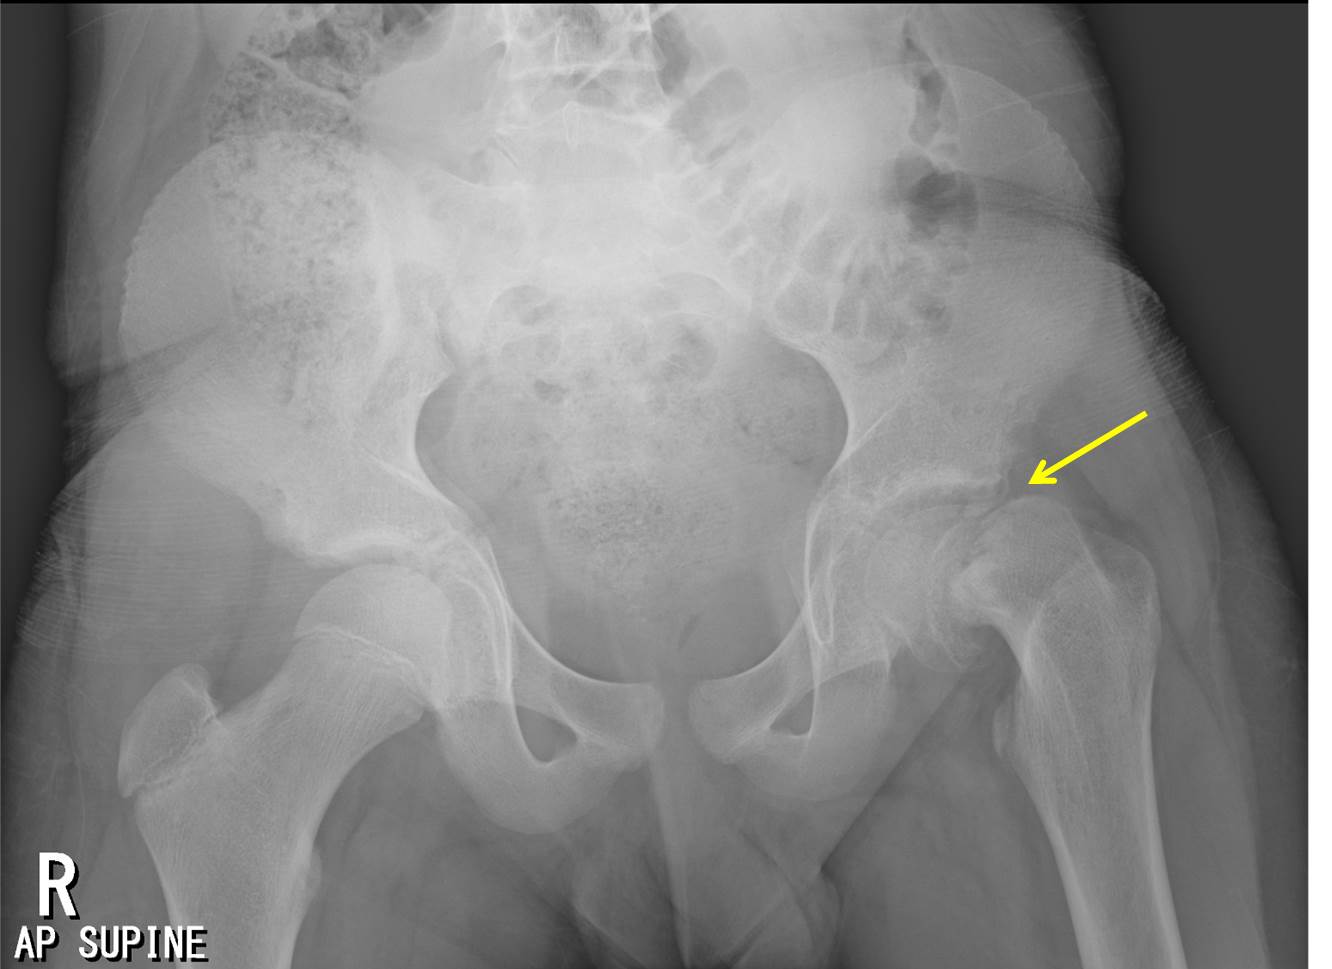

Slipped Capital Femoral Epiphysis | UW Emergency Radiology

faculty.washington.edu

faculty.washington.edu

femoral epiphysis slipped capital radiology scfe hip normal

#Hip #Xray In A #child With Hip Pain Shows A Slipped Capital Femoral

www.pinterest.com

www.pinterest.com

epiphysis femoral slipped xray trauma